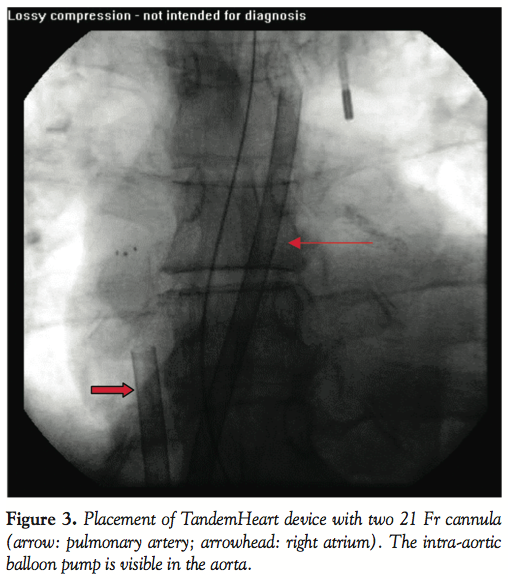

Bilateral femoral venous access was obtained, and 6 Fr sheaths were placed. Femoral venous angiography was performed, revealing near cessation of forward flow. A 6 Fr multipurpose catheter (Cordis Corp.) was advanced into the pulmonary artery through which a 0.035 inch x 260 cm Amplatz ExtraSupport wire (Cook Medical, Bloomington, Indiana) was placed. The 6 Fr sheath in the right femoral vein was removed and serial dilations were made to accommodate the 75 cm 21 Fr TandemHeart outflow cannula which was advanced from the right femoral vein into the pulmonary artery and clamped. A second 75 cm 21 Fr TandemHeart inflow cannula was placed after serial dilations from the left femoral vein and advanced to the right atrium and clamped. After confirming the position angiographically, the TandemHeart cannulae were connected to the intermediary motor via secure wet-to-wet connections and flow was initiated at 3 liters per minute.